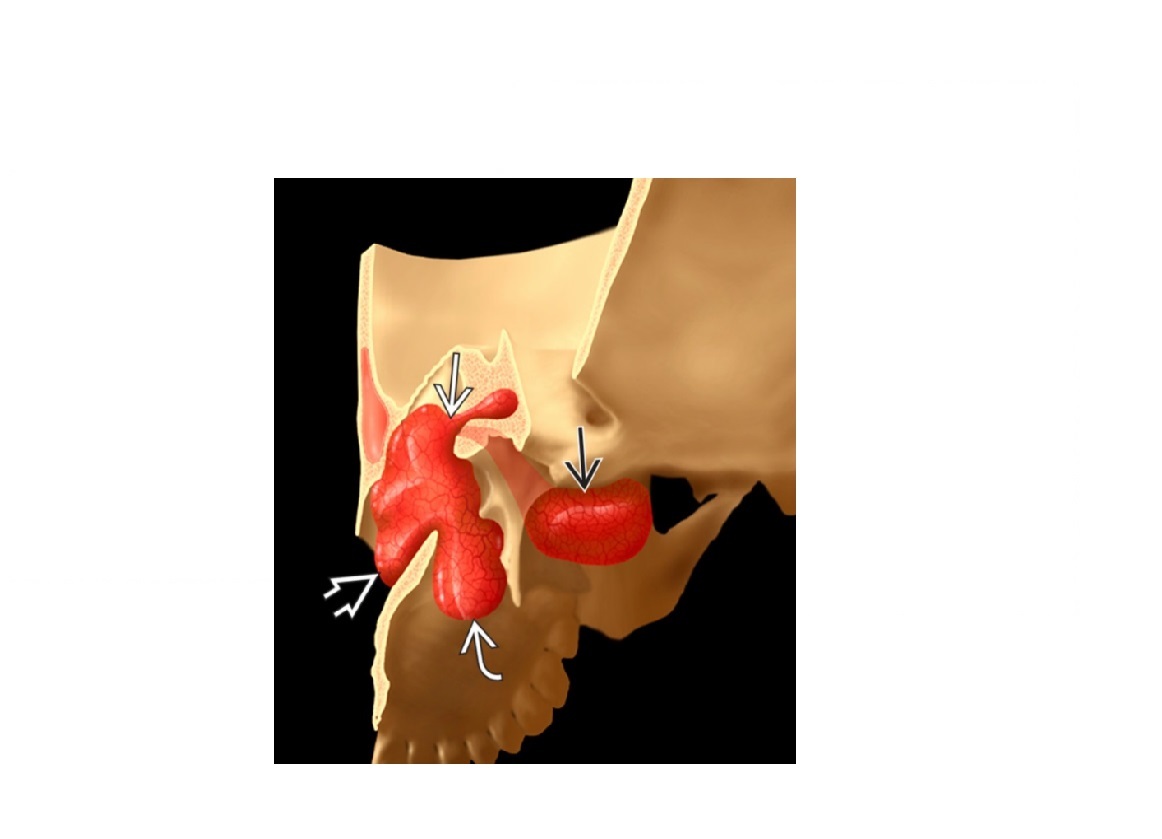

Highly vascular mass in nasopharynx eroding the medial ptyergoid plates and arising from sphenopalatine fossa?

A

Juvenile angiofibroma

Supplied by the internal maxillary artery. Embolise it.